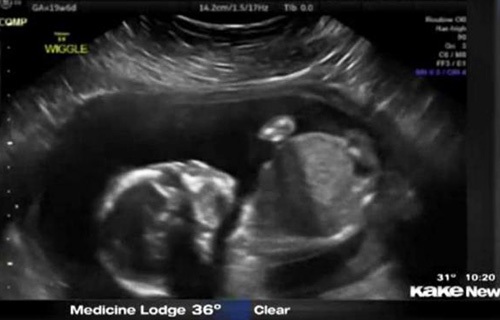

还只有5个月半的胎儿 居然自己打自己的脸,这也太奇葩了,将来可能是个拳王啊。~美国堪萨斯州一个5个月半大的胎儿在母亲子宫内打自己的脸并把自己击倒,这一幕刚好被父母用超声波检测仪记录了下来,并被分享到网上,引得众人称奇。

这对夫妇原本还担心儿子可能会有脑震荡,但护士让他们放心。凡妮莎说,这次的事件导致他们开始考虑儿子的个性:“我们俩都爱终极格斗。所以我们正在讨论他或许会成为一个拳击手?!?/span>